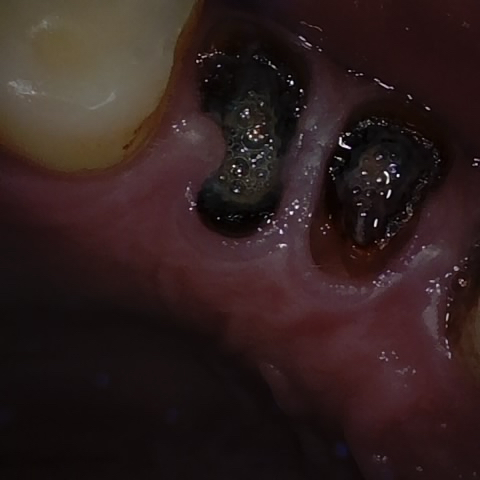

Original Image Rendering Image